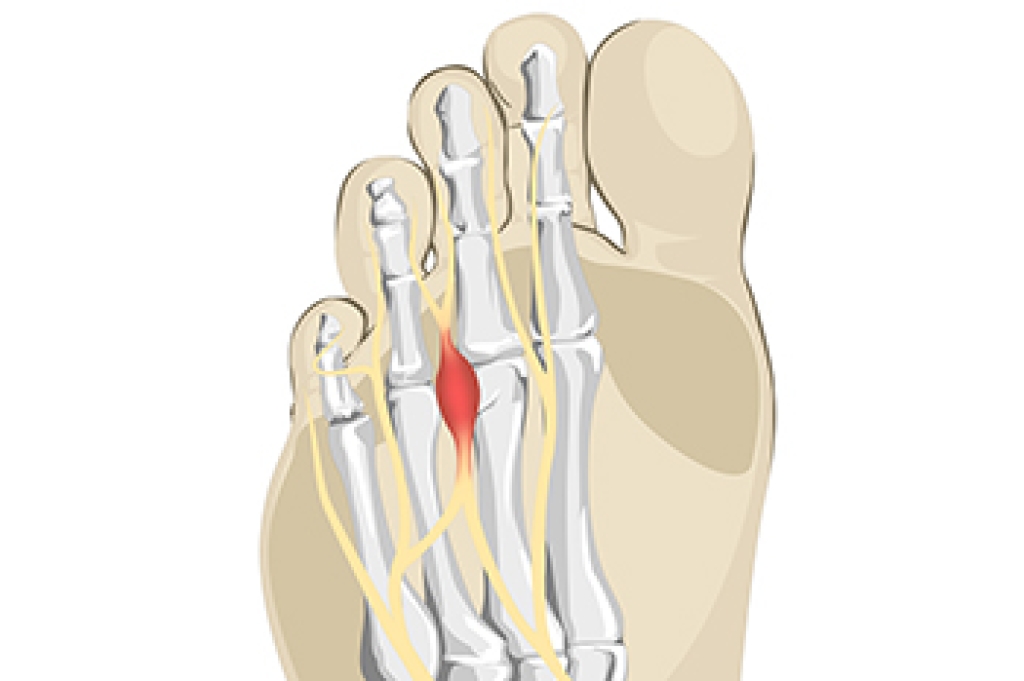

Morton's neuroma is a painful condition that affects the nerves in the foot, specifically between the third and fourth toes. The causes of this condition can be attributed to various factors, such as wearing tight, narrow shoes that compress the toes as well as high heels which increase pressure on the forefoot. Additionally, Morton's neuroma may occur from performing repetitive activities that strain the nerves. Mild relief may be found when the shoes that are worn have a wide-toe box and low heels. Wearing specific types of orthotics may be beneficial in alleviating pain and redistributing pressure. Resting the affected foot as often as possible is important to promote healing. If symptoms persist, it is suggested that you contact a podiatrist for a proper diagnosis and a personalized treatment plan to effectively manage Morton's neuroma.

Morton's neuroma is a painful foot condition that commonly affects the areas between the second and third or third and fourth toe, although other areas of the foot are also susceptible. Morton’s neuroma is caused by an inflamed nerve in the foot that is being squeezed and aggravated by surrounding bones.

- Ill-fitting high heels or shoes that add pressure to the toe or foot

- Jogging, running or any sport that involves constant impact to the foot

- Flat feet, bunions, and any other foot deformities

Morton’s neuroma is a very treatable condition. Orthotics and shoe inserts can often be used to alleviate the pain on the forefront of the feet. In more severe cases, corticosteroids can also be prescribed. In order to figure out the best treatment for your neuroma, it’s recommended to seek the care of a podiatrist who can diagnose your condition and provide different treatment options.